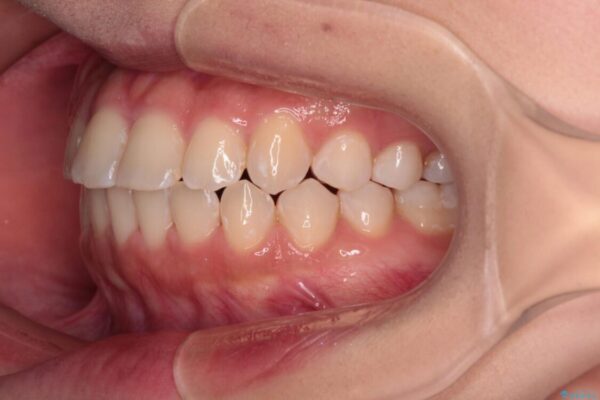

治療途中

• 【モニター】短期間で終わりたい ワイヤー装置での非抜歯矯正 治療途中画像